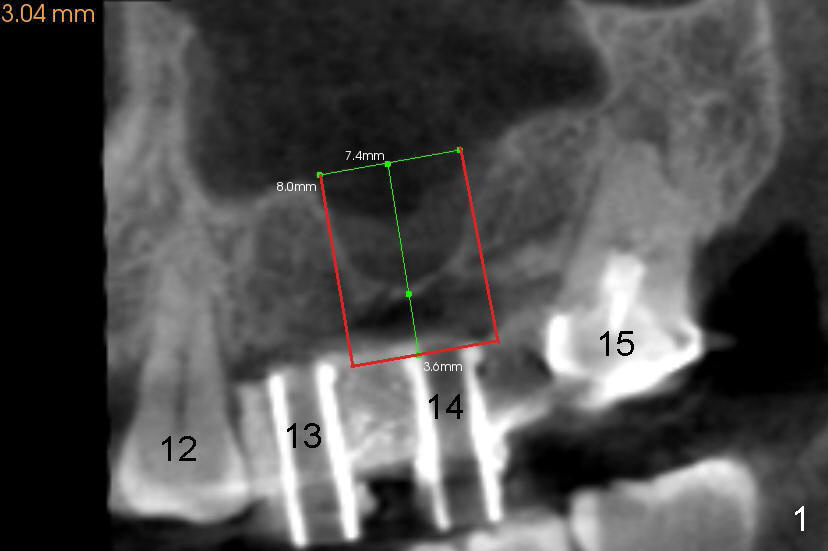

The two cases we discuss early appear to show that implants at the first molar are placed to engage in the mesial aspect of bone to have primary stability (1,2). But sometimes sinus floor may be right above the first molar (Fig.1-4). Fig.1 (CT sagittal) and 2 (coronal) were taken before #15 extraction, whereas Fig.3, 4 (PA) were taken during and immediately after extraction, respectively. A tapered 8x17 mm implant was placed at the site of #15.

In fact, sinus graft has been tried without success (sinus membrane torn, buccal wall difficult to penetrate). The patient refuses to an offer to get a second trial by an expert such as Drs. Borgner and Dunson. Sinus lift appears to be more acceptable.